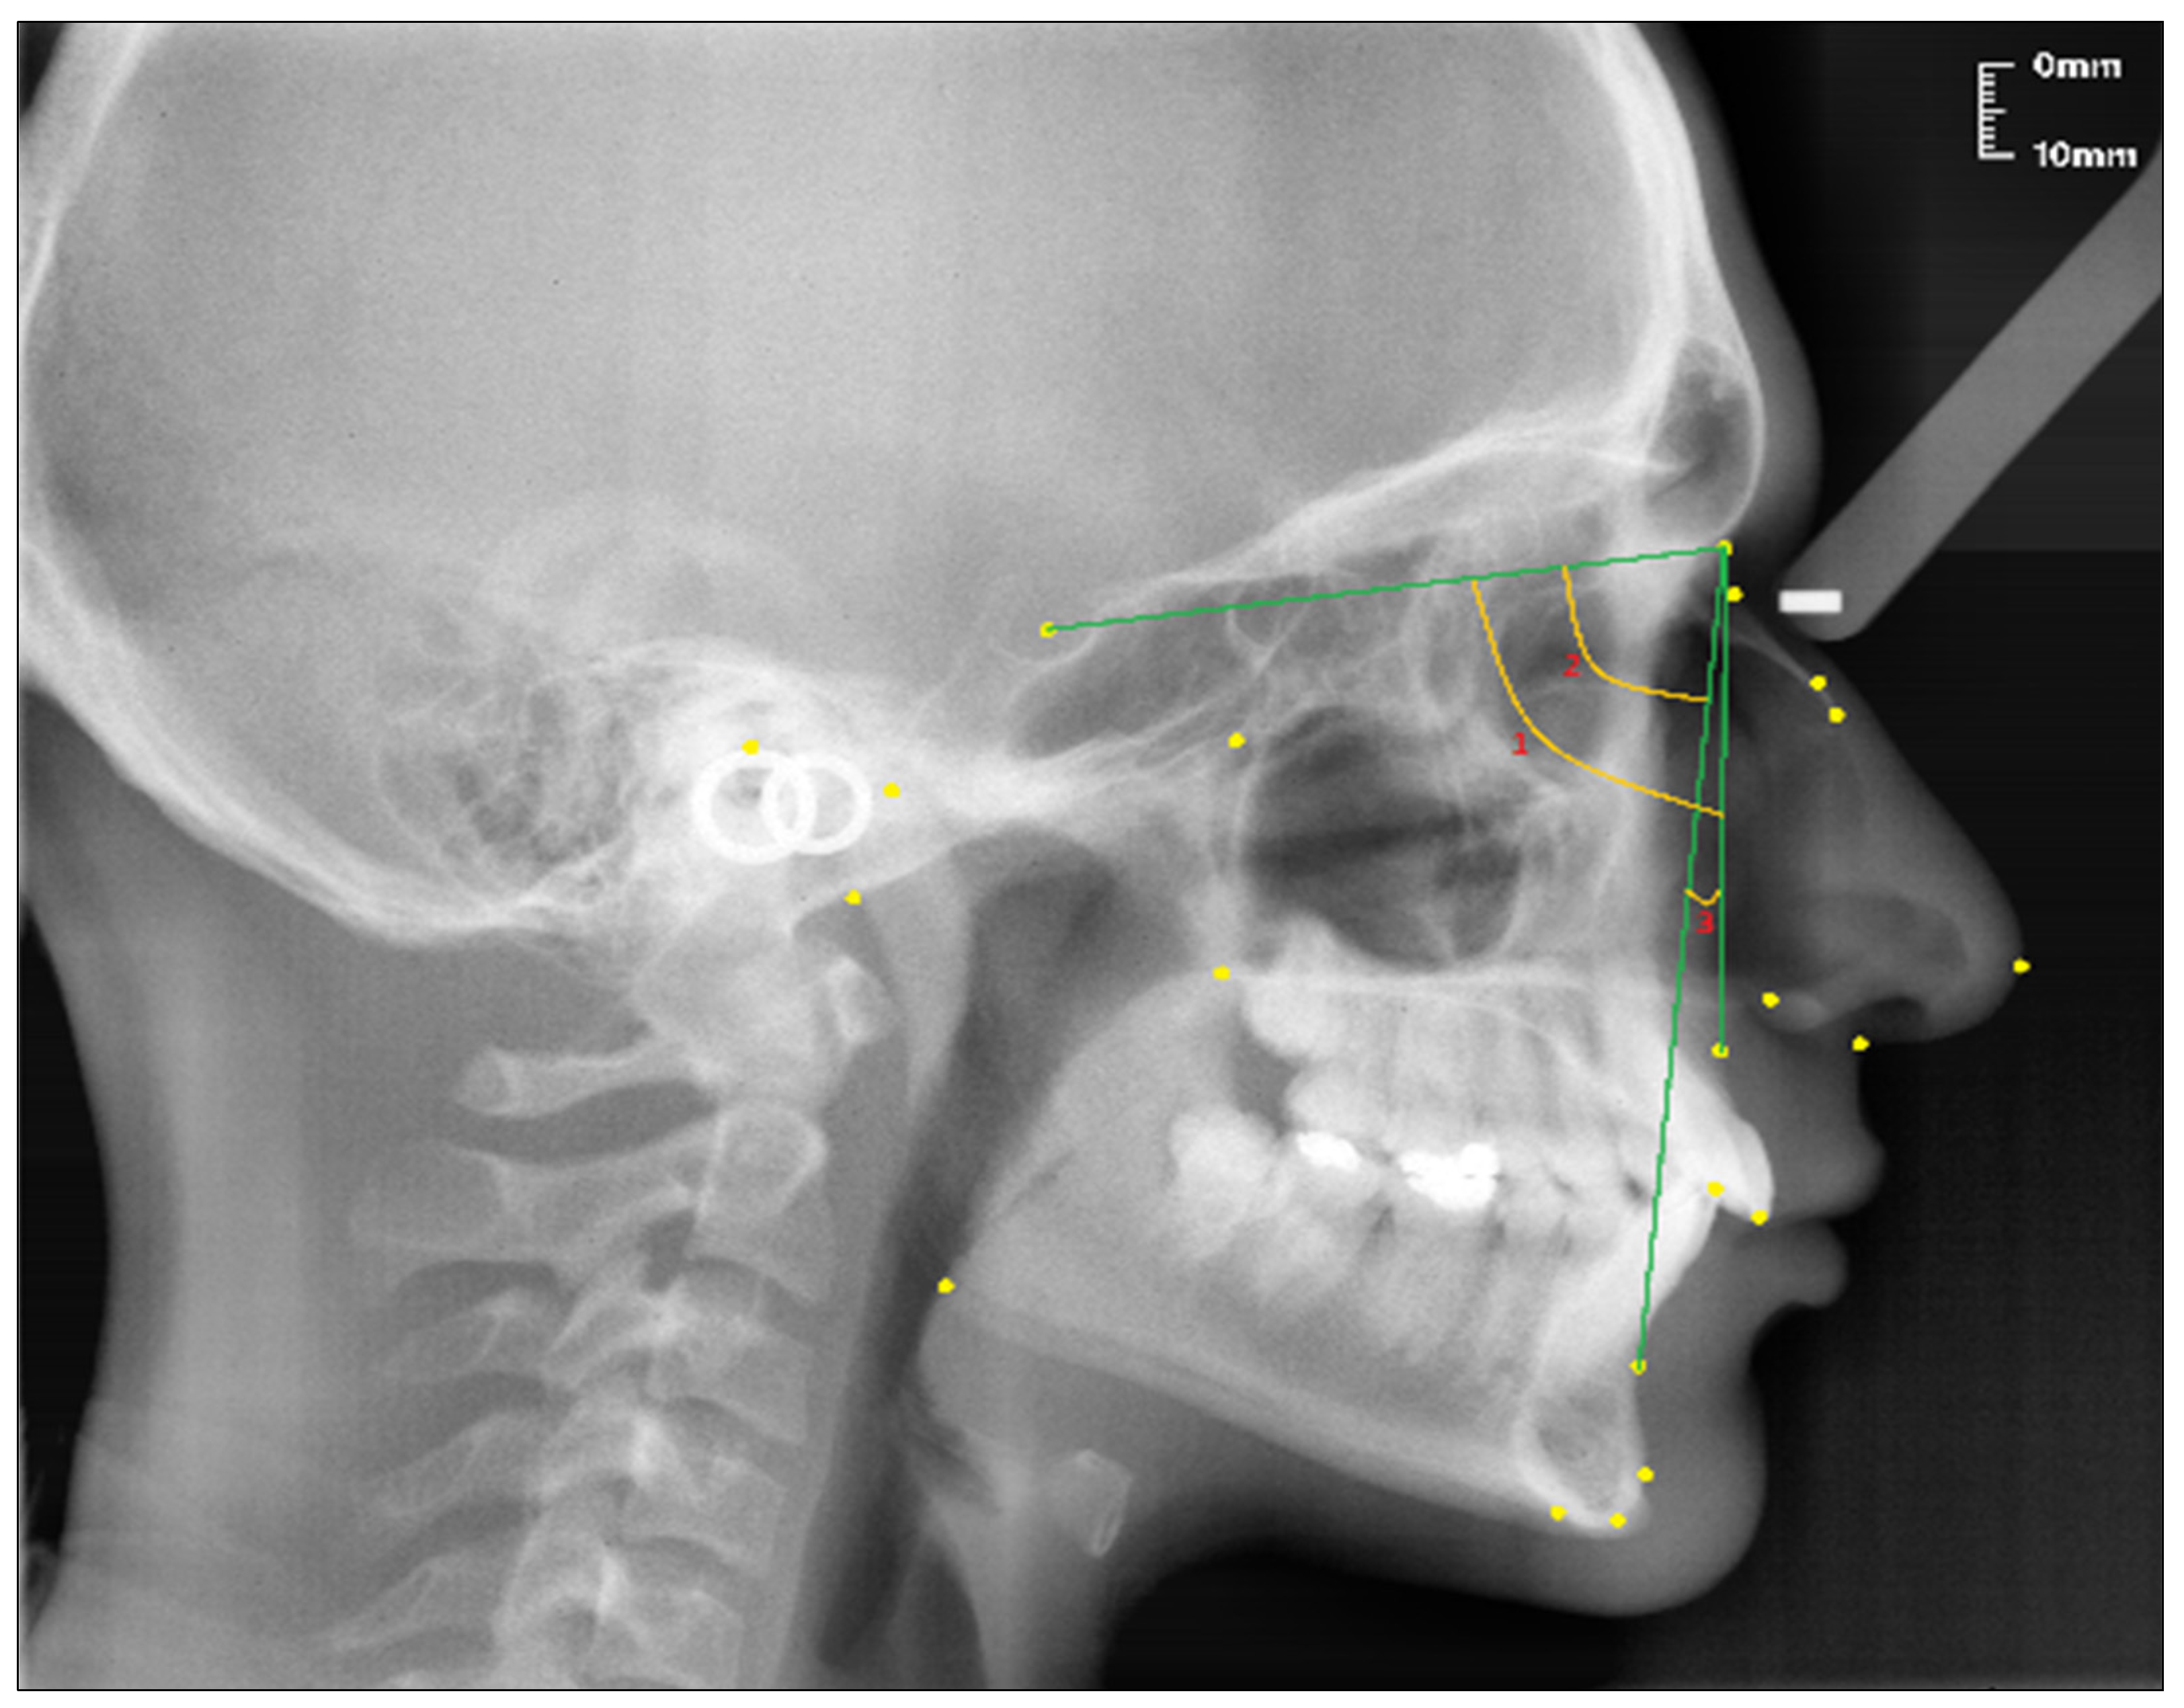

2.2. Cephalometric Analysis

- Sella (S); the center of Sella turcica.

- Nasion (N); the most anterior point of the sutura frontonasalis and the deepest place of the recess in that region.

- Rhinion (R); the most anterior and inferior point on the tip of the nasal bone.

- Subspinal–point A; below the ANS point, the maxilla is the deepest point of the alveolar bone recess.

- Supramental–point B; deepest midline point on the mandible between infradentale and pogonion.

- Anterior nasal spine (ANS) point; the tip of the median, sharp bony process of the maxilla at the lower margin of the anterior nasal opening.

- N1 point; the most concave point of the nasal bone.

- N2 point; the most convex point of the nasal bone.

- Nasion-Rhinion (N-R); the distance between the nasion and the rhinion points.

- Nasion-Anterior nasal spina (N-ANS); the distance between the nasion and the anterior nasal spina points.

- Rhinion-Subspinale (R-A); the distance between the rhinion and the subspinale points.

- Nasion-Subspinale (N-A); the distance between the nasion and the subspinale points.

- Nasal Bone Concavity Angle (Nbone Angle); the posterior angle formed between the N1-N2 line and the N2-R line.

- SNA (°); the angle between the SN line and the NA line.

- SNB (°); the angle between the SN line and the NB line.

- ANB (°); the angle between the lines NA and NB.